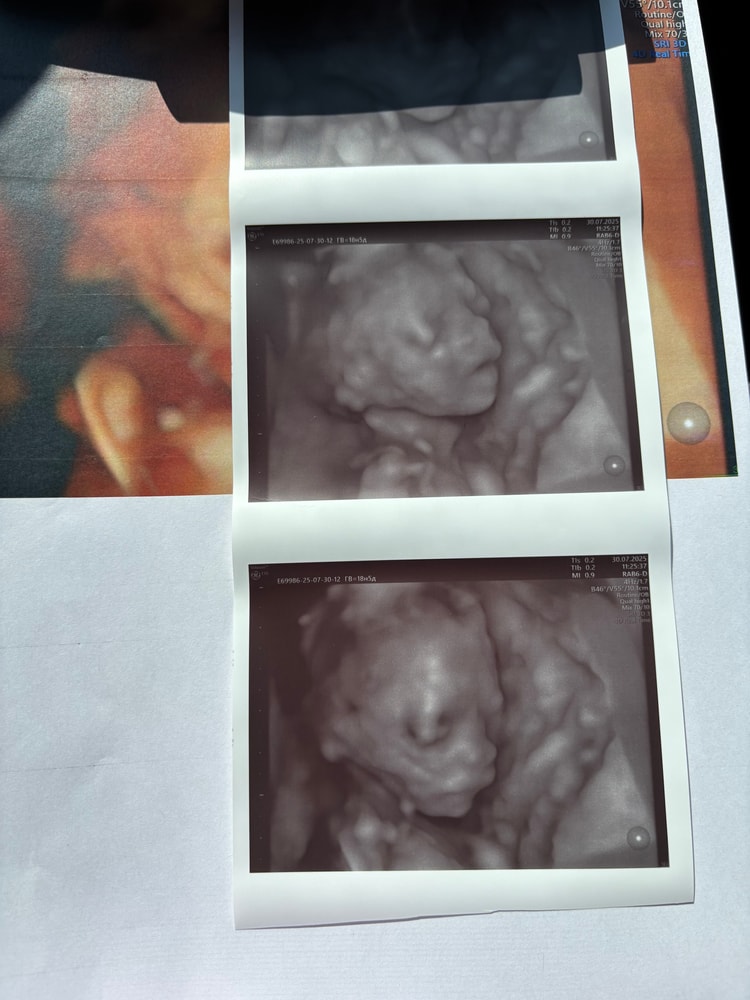

✨ Прошла 2 скрининг, с малышкой все хорошо, развивается. На экране видела как она зевала, и высовывала язычок. Ручками и ножками дергала. Вес уже 334 грамма. Сделали фотки в 3д узи, очень хорошо видно личико. Одну фоточку отрезала и повесила на холодильник 😊 Теперь хожу и любуюсь.